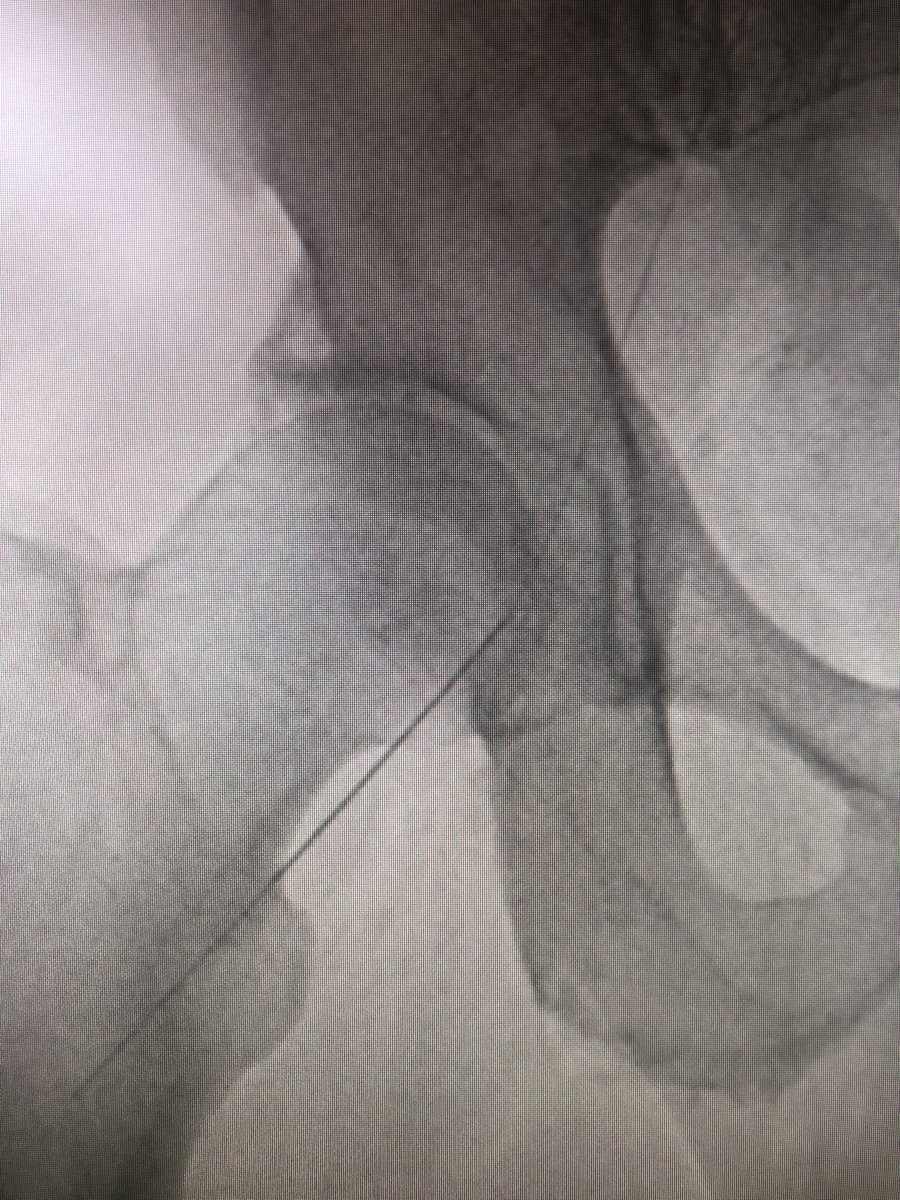

Step 3 - cautiously insert guidewire. #FluoroTheWire as it courses the artery. Observe its behavior and incorporate this into what sheath you should use for the procedure you need. I have started taking a quick #FluoroStore to show angle of needle and wire. #JointCathConference

Step 4 - #AccessAngio through micro access. tip - keep guidewire in and attach #CoPilot and inject. Protects by injecting into vessel and not the wall! #PreventDissection Remember to angle to show SFA and profunda. #JointCathConference